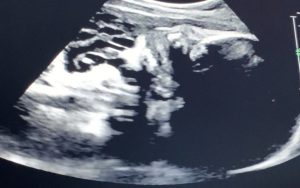

Baby Fulton’s 39 week ultrasound video

Fulton Smiles – ultrasound at 37 weeks